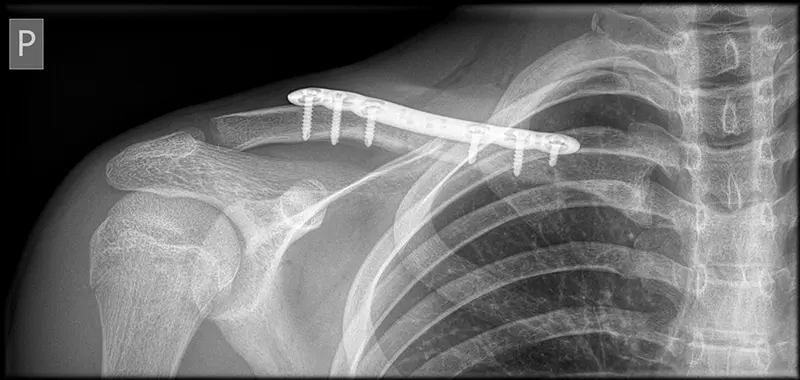

Wskazania do operacji zależą od rodzaju złamania, przemieszczenia fragmentów, obecności uszkodzeń towarzyszących oraz indywidualnych okoliczności pacjenta. W niektórych przypadkach, zwłaszcza gdy złamanie jest przesunięte i nie może być poprawione za pomocą leczenia zachowawczego, konieczna jest interwencja chirurgiczna. Operacja może obejmować umieszczenie płytki i śrub w celu stabilizacji złamanego obojczyka.

Po operacji istnieje okres rekonwalescencji, który wymaga ostrożności przez kilka tygodni. Fizjoterapia i rehabilitacja są często częścią procesu zdrowienia, aby przywrócić pełną funkcjonalność stawu barkowego.